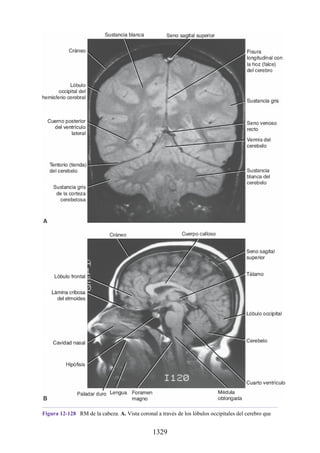

13B). El tendón se invagina en la bolsa por uno de los lados de esta y queda

suspendido dentro de la bolsa por un mesotendón (véase fig. 1-13C). El

mesotendón permite que los vasos sanguíneos se introduzcan en el tendón a lo

largo de su trayectoria. En algunas situaciones, cuando la amplitud de mo